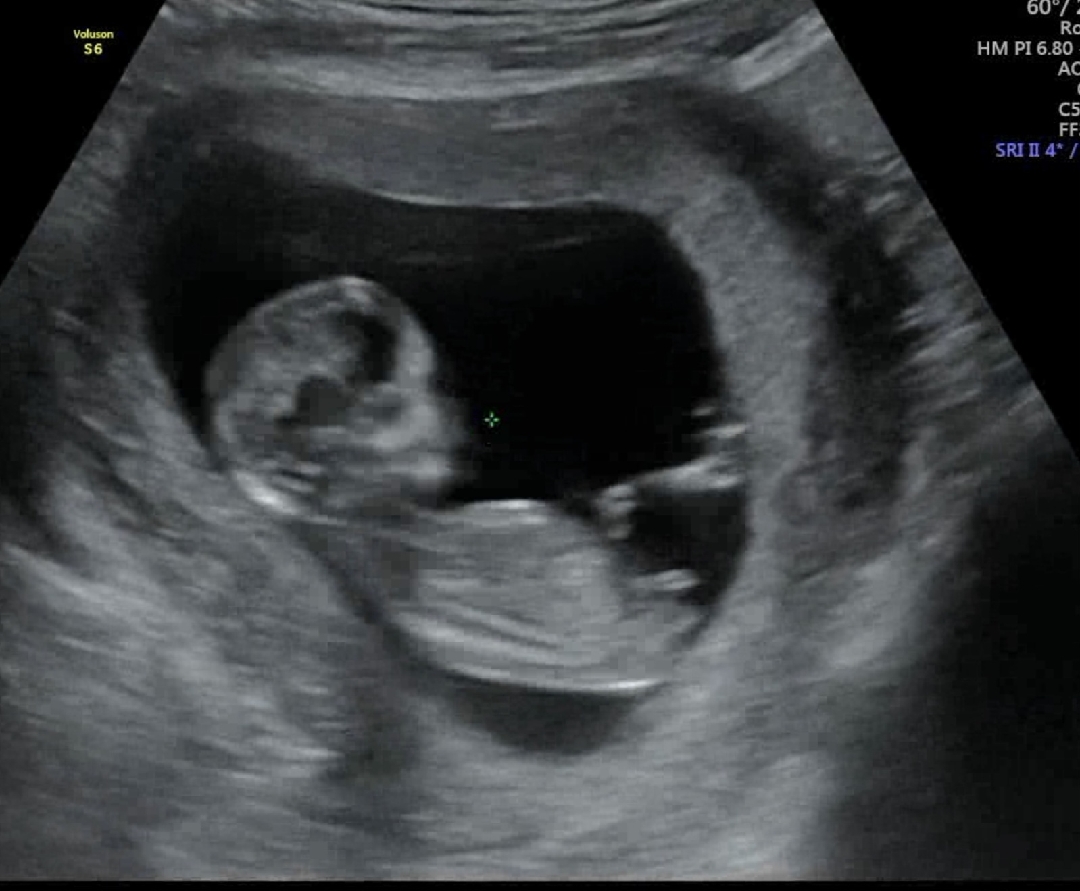

각도법한번봐주세용

궁금해요ㅠㅜ12주6일사진이예용